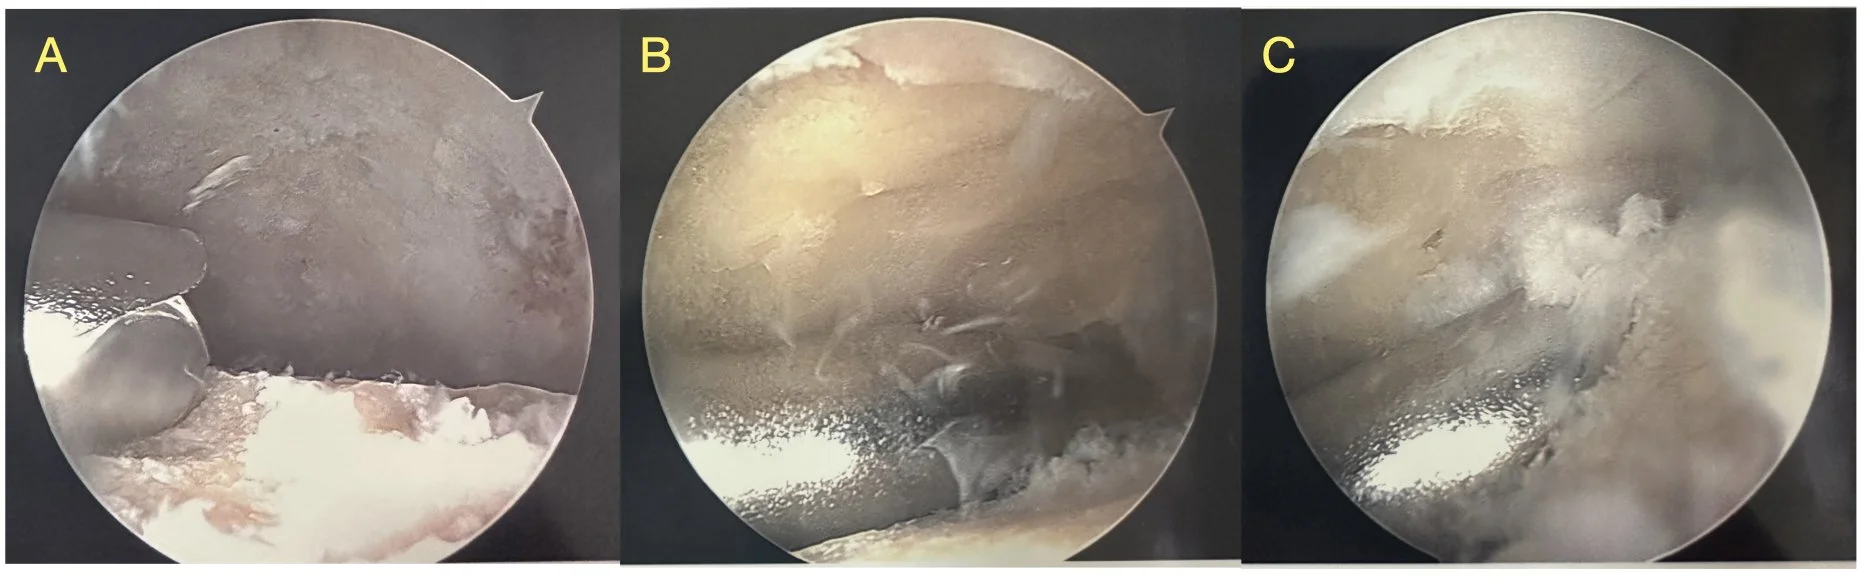

Figure 1: arthroscopic ankle fusion in a patient with end stage arthritis.

Figure 2: arthroscopic view of an ankle joint being prepared for fusion